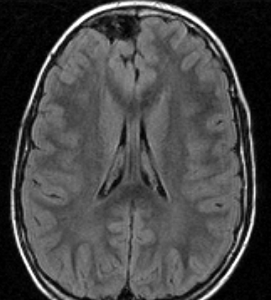

- 脳のところどころに,T2/フレアで何か特定できない高信号がみえます (UBO unidentified bright objects あるいはFASI focal area of signal intensityといいます)

- 病理学的には,髄鞘空洞化(myelin vacuolization, altered myelination),過形成性グリオーシス(hyperplastic gliosis)いわれるものです

- MRIで腫瘍のようにみえますがそうではありません。T2強調画像で白く見えてガドリニウム造影されないのが一般的な特徴です

NF-1に見られる典型的なUBOです。白くにじむように見えるところが,両側の大脳基底核から視床に散在しています。脳幹部にも同時に見られることが多いです。もちろん治療の必用はありません。